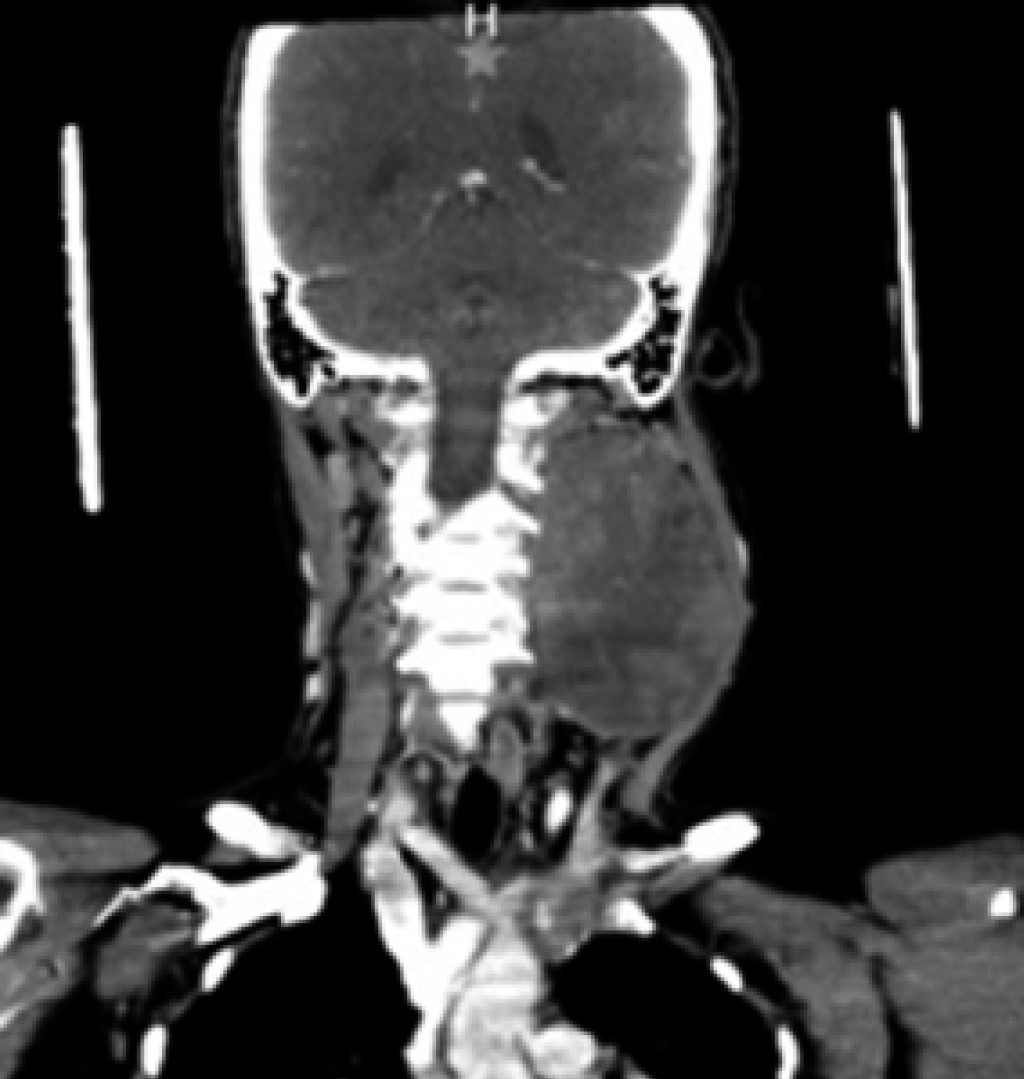

Physical examination revealed the presence of a cervical tumor measuring approximately 12 × 8 × 10 cm, indurated, and fixed to deep planes, covering regions II, III, and Va of the left hemi collar (Figure 1); it was slightly painful on palpation with a 3/10 intensity on VAS, without difficulty in opening the mouth, no facial asymmetry nor airway involvement.

There was no systemic inflammatory response syndrome, hemodynamic instability, or cardiopulmonary compromise. As a diagnostic complement, a CT scan is requested, which reports a large, rounded mass of solid appearance with regular edges, well delimited, heterogeneous, predominantly hypodense, with small areas of lower density inside, without identifying calcifications, with a density between 24 and 37 HU and that after the administration of intravenous contrast presents a density between 33 and 87 HU. It was in the left parapharyngeal level of 6.6 × 7.5 × 9.2 cm, as a left parapharyngeal space lesion with a suspected branchial cyst versus pleomorphic adenoma versus hemorrhagic branchial cyst (Figures 2, 3 and 4).